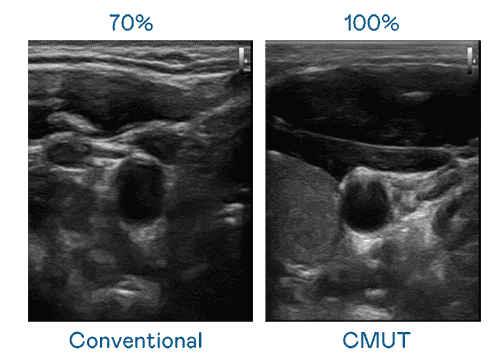

CMUT 技术是一种用电容式微机电元件来产生超音波讯号的技术。。。。与传统 PZT 压电式技术相比,,CMUT 频宽增加 30%,,,更宽频的超音波讯号让影像解析度大幅提升,,,,是实现高影像品质医疗超音波扫描、、、、促进精准医疗发展的关键技术。。。。

大频宽带来超清晰影像

超音波影像的解析度高低,,首先取决于探头能发出的讯号频宽。。。壹号平台 CMUT 可提供高清晰的超音波讯号,,,,提供高频宽、、、高灵敏度、、、影像纹理细节更高的超音波影像,,协助医护人员缩短影像判读时间及利用精准的医疗影像进行诊断。。。